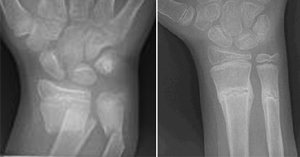

Emergency Medicine Pearls Pitfalls For Treatment Of Pediatric Distal Radius Fractures Acep Now

Emergency Medicine Pearls Pitfalls For Treatment Of Pediatric Distal Radius Fractures Acep Now from www.acepnow.com

Obviously not a broken wrist or even a recent injury. Up to 3 months with a cast. Scar tissue all ready well healed. Patients who sustain a broken wrist may be treated in a cast or may need surgery for treatment. You should pay attention if the problem persists. A broken wrist is one of the most common forearm injuries. A forearm fracture can occur near the wrist, the middle of the forearm or near the elbow. Common symptoms of a wrist fracture include